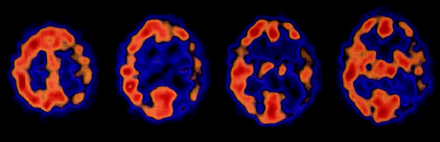

我们评估了天赋和T2图像7的9个病人。一个醉酒驾车和一个质子density-weighted形象(PD)除了可用(表2和图1中,通过D)。除了一个病人(例3)检查后整体疾病持续时间的三分之一。所有七个病人显示皮层信号增加,而只有两个病人显示hyperintense基底神经节。受影响的大脑区域通常是颞叶(所有的病人),脑岛和海马体(6例),其次是额叶、顶叶、枕叶和扣带回(5例)。病人呈现焦迹象,相应的MRI大脑区域受到影响:额叶是显示失用症和失语症患者的影响,在病人显示hypacusis颞叶,枕叶视觉障碍患者。

下面的案例报告是选择来说明一个典型的MRI显示信号增加大脑皮层区域在一个案例中(8例)和SPECT异常在另一个(例4)。

他住院两个月后出现症状。核磁共振成像显示信号增加额叶和颞叶T2。天赋还显示一个信号增加parieto-occipital叶和海马。开始三个月后,病人被送去精神病院,因为他行为异常发达,成为害怕电。四个月后开始,他的神经状态仍然是正常的,除了抑制眉间反射和轻度痴呆(21 30分的细微精神状态检查)。当时MRI显示更少的参与fronto-parieto-occipital叶但轻微的信号变化的基底神经节(右尾状核头在左边)(见图1一个)。SPECT显示低灌注的左颞叶。但是没有PSWCs脑电图显示间歇性theta-delta活动。病人在疾病发作10个月后死亡。